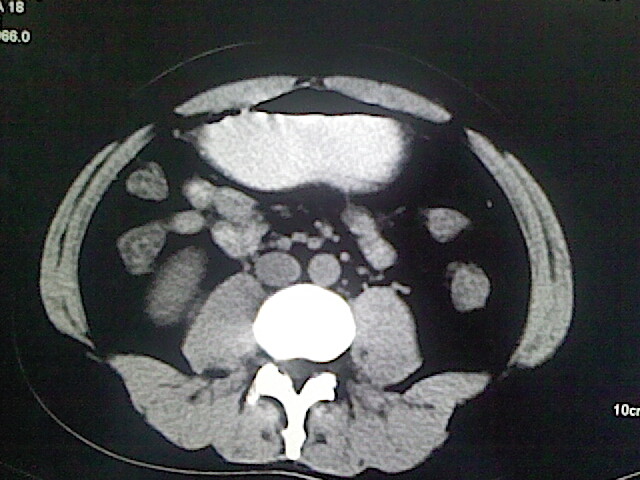

以下是引用卜一在2009-3-14 9:49:00的发言:[br]胆囊萎缩,胆囊壁不规则增厚,内部结构模糊,增强明显强化。另:肝左叶外侧段肝囊肿。支持:慢性胆囊炎!高度可疑:胆囊癌!

以下是引用余辉在2009-3-14 8:48:00的发言:[br]1)慢性胆囊炎。2)肝左叶外侧段肝囊肿。3)脂肪肝。[br]支持,胆囊萎缩,密度增高,不知b超具体有何提示,钙胆汁?结石?

以下是引用jiangjing在2009-3-14 10:18:00的发言:[br]1)慢性胆囊炎。2)肝左叶外侧段肝囊肿。3)脂肪肝。4.】建议行肝功能检查